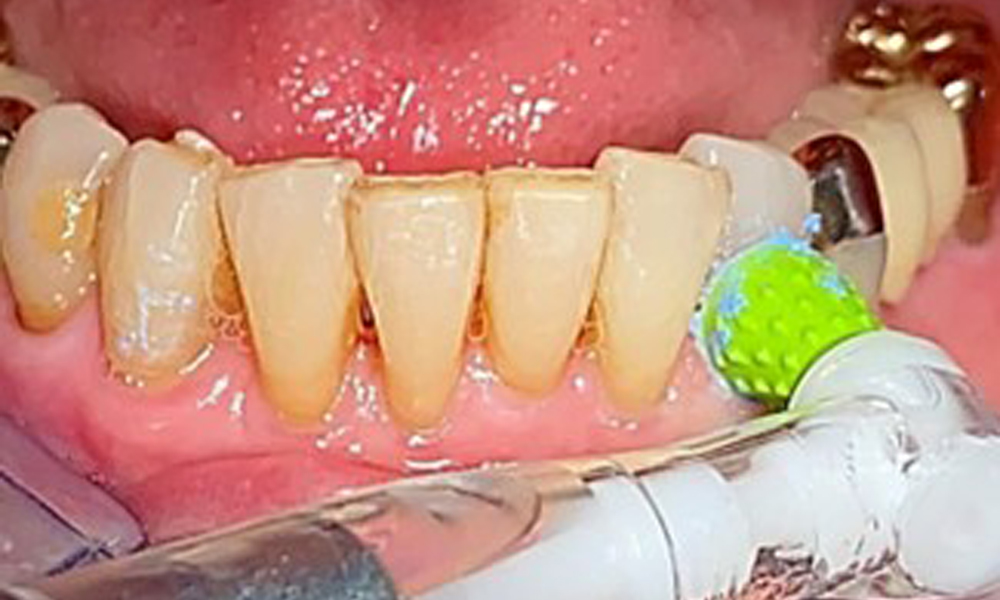

Eine Einbüschelbürste insbesondere für die Teleskope sind empfehlenswert (Abb. 8) und Interdentalbürstchen mit der passenden Größe sind der Patientin aufzuzeigen (Abb. 9). Die Patientin setzt diese Empfehlungen der häuslichen Mundhygiene seit vielen Jahren um und wird im Rahmen der unterstützenden professionellen Präventionssitzung bestärkt, dies weiterhin zu tun.

Für die Restaurationsränder und Zahnzwischenräume und Implantatoberflächen kann das Pulverstrahlgerät mit einem niedrig-abrasiven Pulver zum Einsatz zur Entfernung von Biofilm kommen (Abb. 12). Durch selektives Polieren (Abb. 13) sollte eine Glättung aller weniger sensiblen Bereiche erfolgen, da die bakterielle Wiederanhaftung reduziert wird. (9)